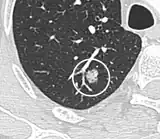

Lung nodule abutting a pulmonary cyst.[9]

• A lung nodule abutting a pulmonary cyst is a rare finding, yet indicating cancer.[9]

• Bubble-like lucencies in the nodule indicate cancer:[9]